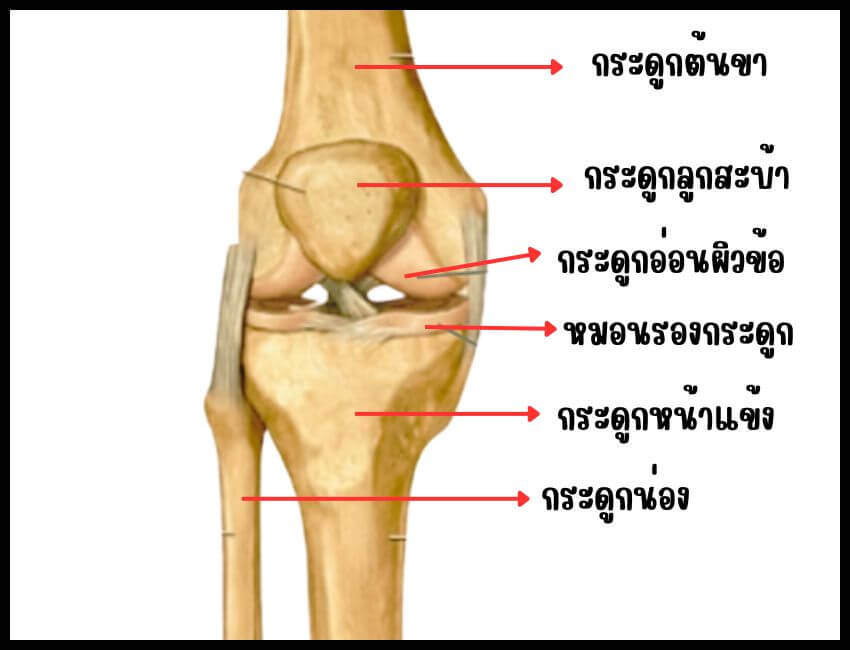

โครงสร้างกระดูกข้อเข่าประกอบด้วยกระดูก 3 ส่วน คือ กระดูกต้นขา ( femur) และ กระดูกหน้าแข้ง ( tibia) และ กระดูกลูกสะบ้า ที่ผิวกระดูกต้นขาจะปกคลุมด้วย กระดูกอ่อนผิวข้อ ( articular cartilage) ซึ่งมีลักษณะเป็นผิวเรียบมัน ทำหน้าที่ลดแรงเสียดทาน เพิ่มการเคลื่อนไหวให้กับข้อเข่า กระดูกอ่อนผิวข้อ ประกอบด้วย น้ำ 80 % คอลลาเจนที่มีสารประกอบโปรตีนชื่อว่า “โปรติโอไกลแคน” ( proteoglycan) ร่วมกับโปรตีนชนิดอื่น ๆ เล็กน้อย บริเวณกระดูกอ่อนผิวข้อจะไม่มีเส้นเลือดมาเลี้ยงโดยตรง แต่จะได้รับสารอาหารผ่านทางน้ำหล่อเลี้ยงข้อ